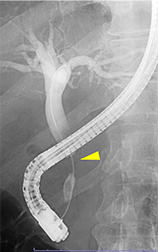

総胆管結石や悪性腫瘍(膵癌、胆道癌)などによって胆道の流れが滞り、黄疸や感染がみられる場合はプラスチックや金属性のステントを胆管に挿入して胆汁の流れをよくします。

膵癌による胆管狭窄

胆管ステント留置後